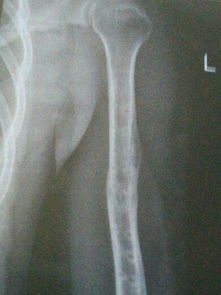

大胆一点... 由于外力撞击、摔倒等原因导致的骨头受伤,如骨折、关节脱位等,是引起骨头痛的常见原因。此类疼痛往往较为剧烈,且与受伤部位直接相关。